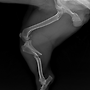

| 양측 골반다발성 골절+ 발목 골절(끊어짐) --교통사고 | 25.03.07 |